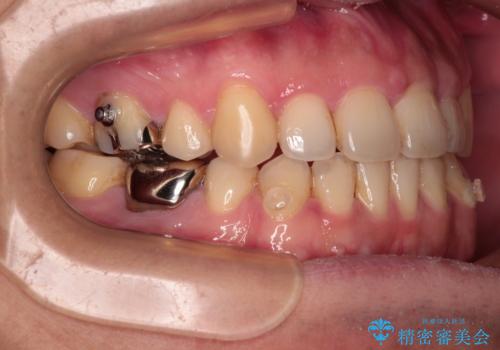

- 抜歯矯正の後戻りを気にして来院された患者様です。

舌の突出癖によるオープンバイトになり、前歯の叢生が後戻りしていました。

舌のトレーニングを行いながら、インビザラインを用いて矯正治療を行うこととしました。

インビザラインの特性を活用して奥歯の咬み合わせを圧下させることで、前歯のオープンバイトを改善さえることができました。